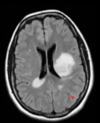

In the image below is a patients with multiple sclerosis sagittal scan from the brain. What are the white area in this image a sign of?

1 - myelinated areas

2 - neuronal cell bodies

3 - unmyelinated areas

4 - glial scars called sclerela

A

When we talk about lesions in multiple sclerosis, they can be - juxtacortical/intracortical - periventricular - infratentorial - spinal cord Which of the above areas of the CNS matches the following: - lesion next to and with direct contact with the lateral ventricles

- periventricular - image shows bright demyelination plaques around the lateral ventricles